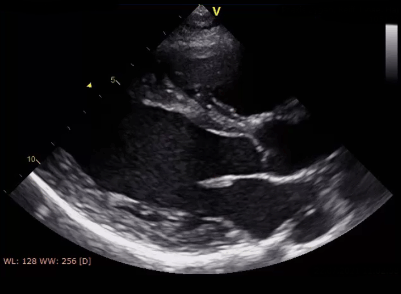

Der Ultraschall des Herzens dient vor allem der Beurteilung von Herzklappen, Herzpumpfunktion dun sonstiger Herzstrukturen. Die Untersuchung erfolgt in Linksseitenlage und kann am Monitor verfolgt werden. [mehr]

Eine transösophageale Echo-kardiographie (TEE) erfolgt mit leichter Sedierung. Eine Narkose ist nur in Ausnahmefällen nötig. Bei dieser Untersuchung kann oft speziellen Fragestellungen (z.B. Herzklappenerkrankungen) nach- gegangen werden. [mehr]